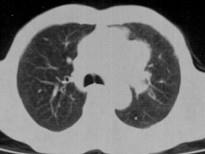

问题 60岁,男,有长期抽烟史,左声带麻痹、声音嘶哑2个月,请结合胸片和CT图,选出最可能的诊断 ( )

选项 A.肺癌 B.肺结核 C.尘肺 D.肺炎 E.肺结节病

答案 A